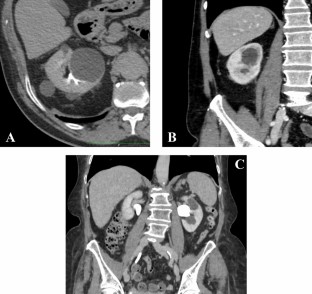

Simple renal cysts are a common finding during abdominal imaging assessment. The incidence increases with age and it is higher in male gender. Parapelvic cysts are a subset of simple cysts that arise within the renal parenchyma, adjacent to the renal sinus, characterized by being generally single, larger, and incompletely surrounded by renal parenchyma. Noteworthy, parapelvic cysts are a rare and understudied condition which, although considered clinically insignificant due to the absence of influence on renal function, still have a controversial aetiopathogenesis. On the other hand, urological management and differential diagnosis have been thoroughly investigated. The aim of our review is to provide an overall vision on this rare condition, usually misdiagnosed and underestimated, on the basis of more recent data. An accurate differential diagnosis of parapelvic cysts can lead to the identification of treatable conditions such as Fabry disease, autosomal dominant polycystic kidney disease, polycystic liver disease and tuberous sclerosis complex disease.

Tarzamni MK, Sobhani N, Nezami N, Ghiasi F (2008) Bilateral parapelvic cysts that mimic hydronephrosis in two imaging modalities: a case report. Cases J 1(1):161. https://doi.org/10.1186/1757-1626-1-161 (PMID:18801196;PMCID:PMC2577646)

Ma TL, Neild GH (2013) Parapelvic cyst misdiagnosed as hydronephrosis. Clin Kidney J 6(2):238–239. https://doi.org/10.1093/ckj/sfs189 (Epub 2013 Feb 1. PMID: 26019858; PMCID: PMC4432443)

Choi HS, Kim CS, Bae EH, Ma SK, Kim SW (2019) Bilateral parapelvic cyst misdiagnosed as hydronephrosis. Chonnam Med J 55(1):65. https://doi.org/10.4068/cmj.2019.55.1.65 (Epub 2019 Jan 25. PMID: 30740344; PMCID: PMC6351317)

Koratala A, Alquadan KF (2018) Parapelvic cysts mimicking hydronephrosis. Clin Case Rep 6(4):760–761. https://doi.org/10.1002/ccr3.1431 (PMID:29636957;PMCID:PMC5889270)